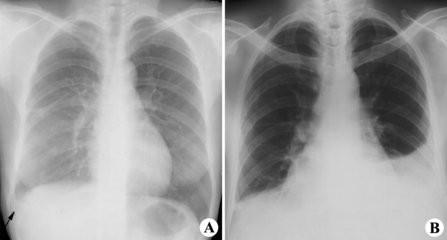

5、X线检查 胸部积液,检查发现患侧肺部呈大片密度均匀一致阴影。